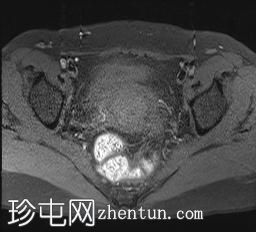

轴位

T2加权像

可见局部晚期浸润性内生型宫颈癌,肿瘤大小为30 x 32 x 48 mm。该肿瘤已侵犯宫颈前唇和后唇的深层间质,以及子宫肌层的下段。

此外,肿瘤还累及宫旁组织。影像学检查发现异常淋巴结肿大,最大短轴直径(SAD)为10 mm,位于髂总血管分叉处和髂内动脉链下方。该淋巴结肿大在弥散加权成像(DWI)上显示水限制,且增强扫描后可见强化。